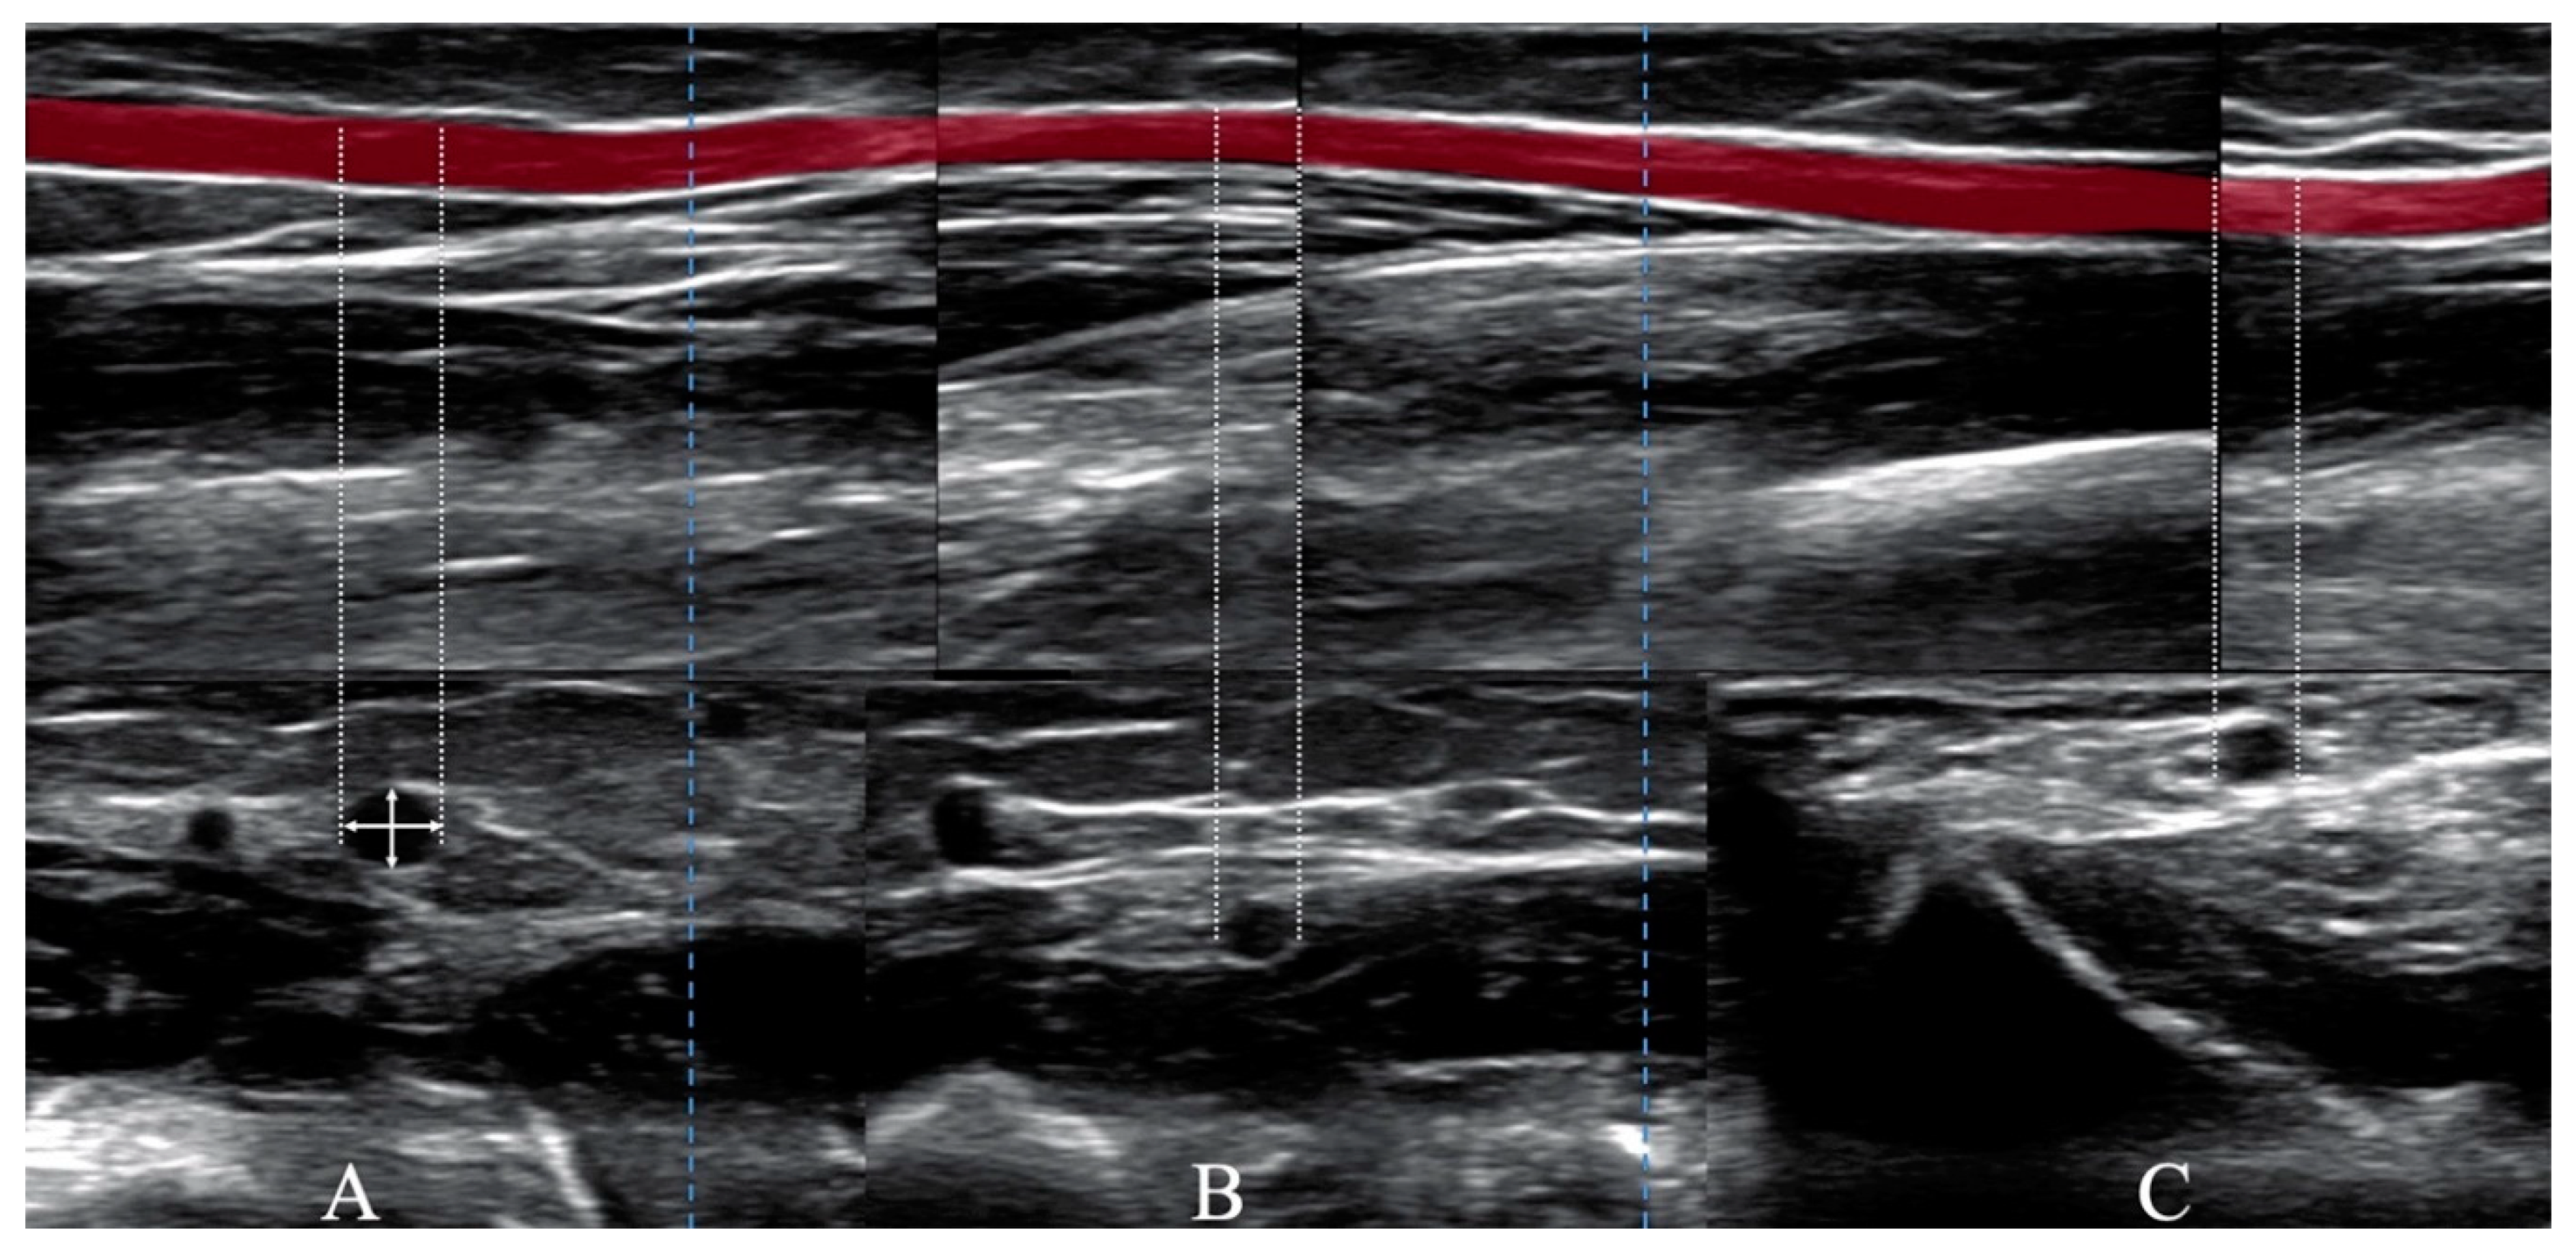

Arterial angiography was performed to observe intra-arterial complications. Perforation of the artery wall occurred in ten (9%) and ten (12%) patients in the larger and smaller groups, respectively. To prevent the growth of hematoma, balloon angioplasty in place of perforation was performed (Figure 3).

4.1.4. Forearm Artery Perforation after CAG/PCI

Artery perforation is a vascular complication with unknown incidence. Knowledge of this complication is based mostly on case reports and very limited data from TRA/TUA efficacy and safety trials [6,20,22]. Our data suggest that this complication could be diagnosed more often if final angiograms of RA or UA after CAG/PCI were performed. Artery perforation can be the basis of other complications radial artery occlusion, small and large hematoma, bleeding, pseudoaneurysms or a-v fistula. If this complication occurs, it could be managed conservatively with prolonged external compression, balloon angioplasty or the implantation of a stentgraft. Early diagnosis and proper treatment of artery perforation could lead to a reduction of the rate of local complications (Figure 3).

Figure 3. Angiograms of perforated UA. (A) vascular sheats (arrowhead), ulnar artery (arrow), (B) perforation of the artery (arrow), (C) balloon angioplasty (arrow), (D) artery without perforation (arrow).